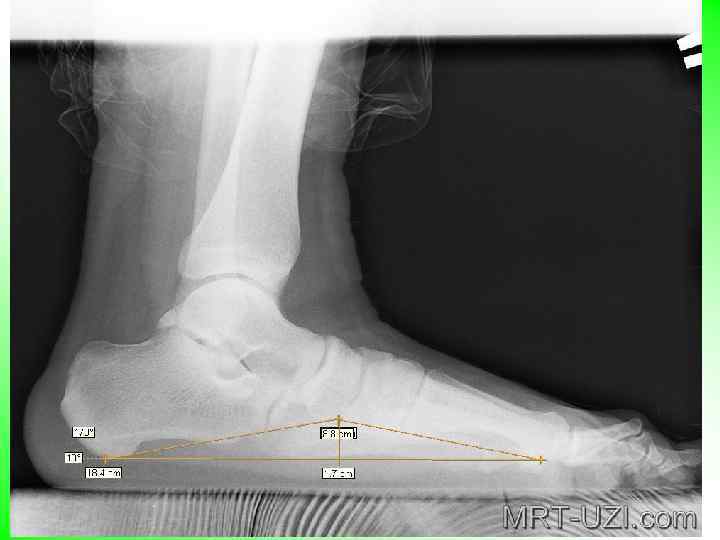

• Радиологиялық зерттеу: Бұл әдіс басқа мәліметтерді толықтырады. Жалпақ табандылық дәрежесін және табан сүйектерінің орналасуын анықтау үшін науқасты тұрғызып бүйір проекциясында сирақты 3 -4 см қамтап түсіру керек. Рентгенограммада қайықтәрізді және сына тәрізді сүйектер арасындағы буындардың төменгі жиегі ұшымен, 1 -табан сүйегінің табандық контуры және өкше төмпегінің төменгі контурынан үшбұрыш түзіледі. Бойлық күмбездің бұрышы мен биіктігін анықтайды-қайықтәріздісынатәрізді буынның төменгі нүктесінен перпендикуляр горизонтальды сызыққа дейін. Қалыпты жағдайда а=125 -130 0, h=36 -39 мм, жалпақ табандылықта бойлық күмбездің бұрышы үлкейеді, ал биіктігі азаяды(1 табл) Көлденең жалпақ табандылық кезінде деформацияның айқын белгісі 1 -табан сүйегімен 1 -бақайдың бұрыштық ауытқуы. Рентгенограммада 1 - 2 табан сүйегі және 1 бақайдың тік осіне сәйкес үш тура линия жүргізеді. Ауытқу дәрежесі градуспен анықталады.

Жалпақ табандылықтың рентгенологиялық диагностикасы: а және hтабанның бойлық күмбезінің бұрышы және биіктігі